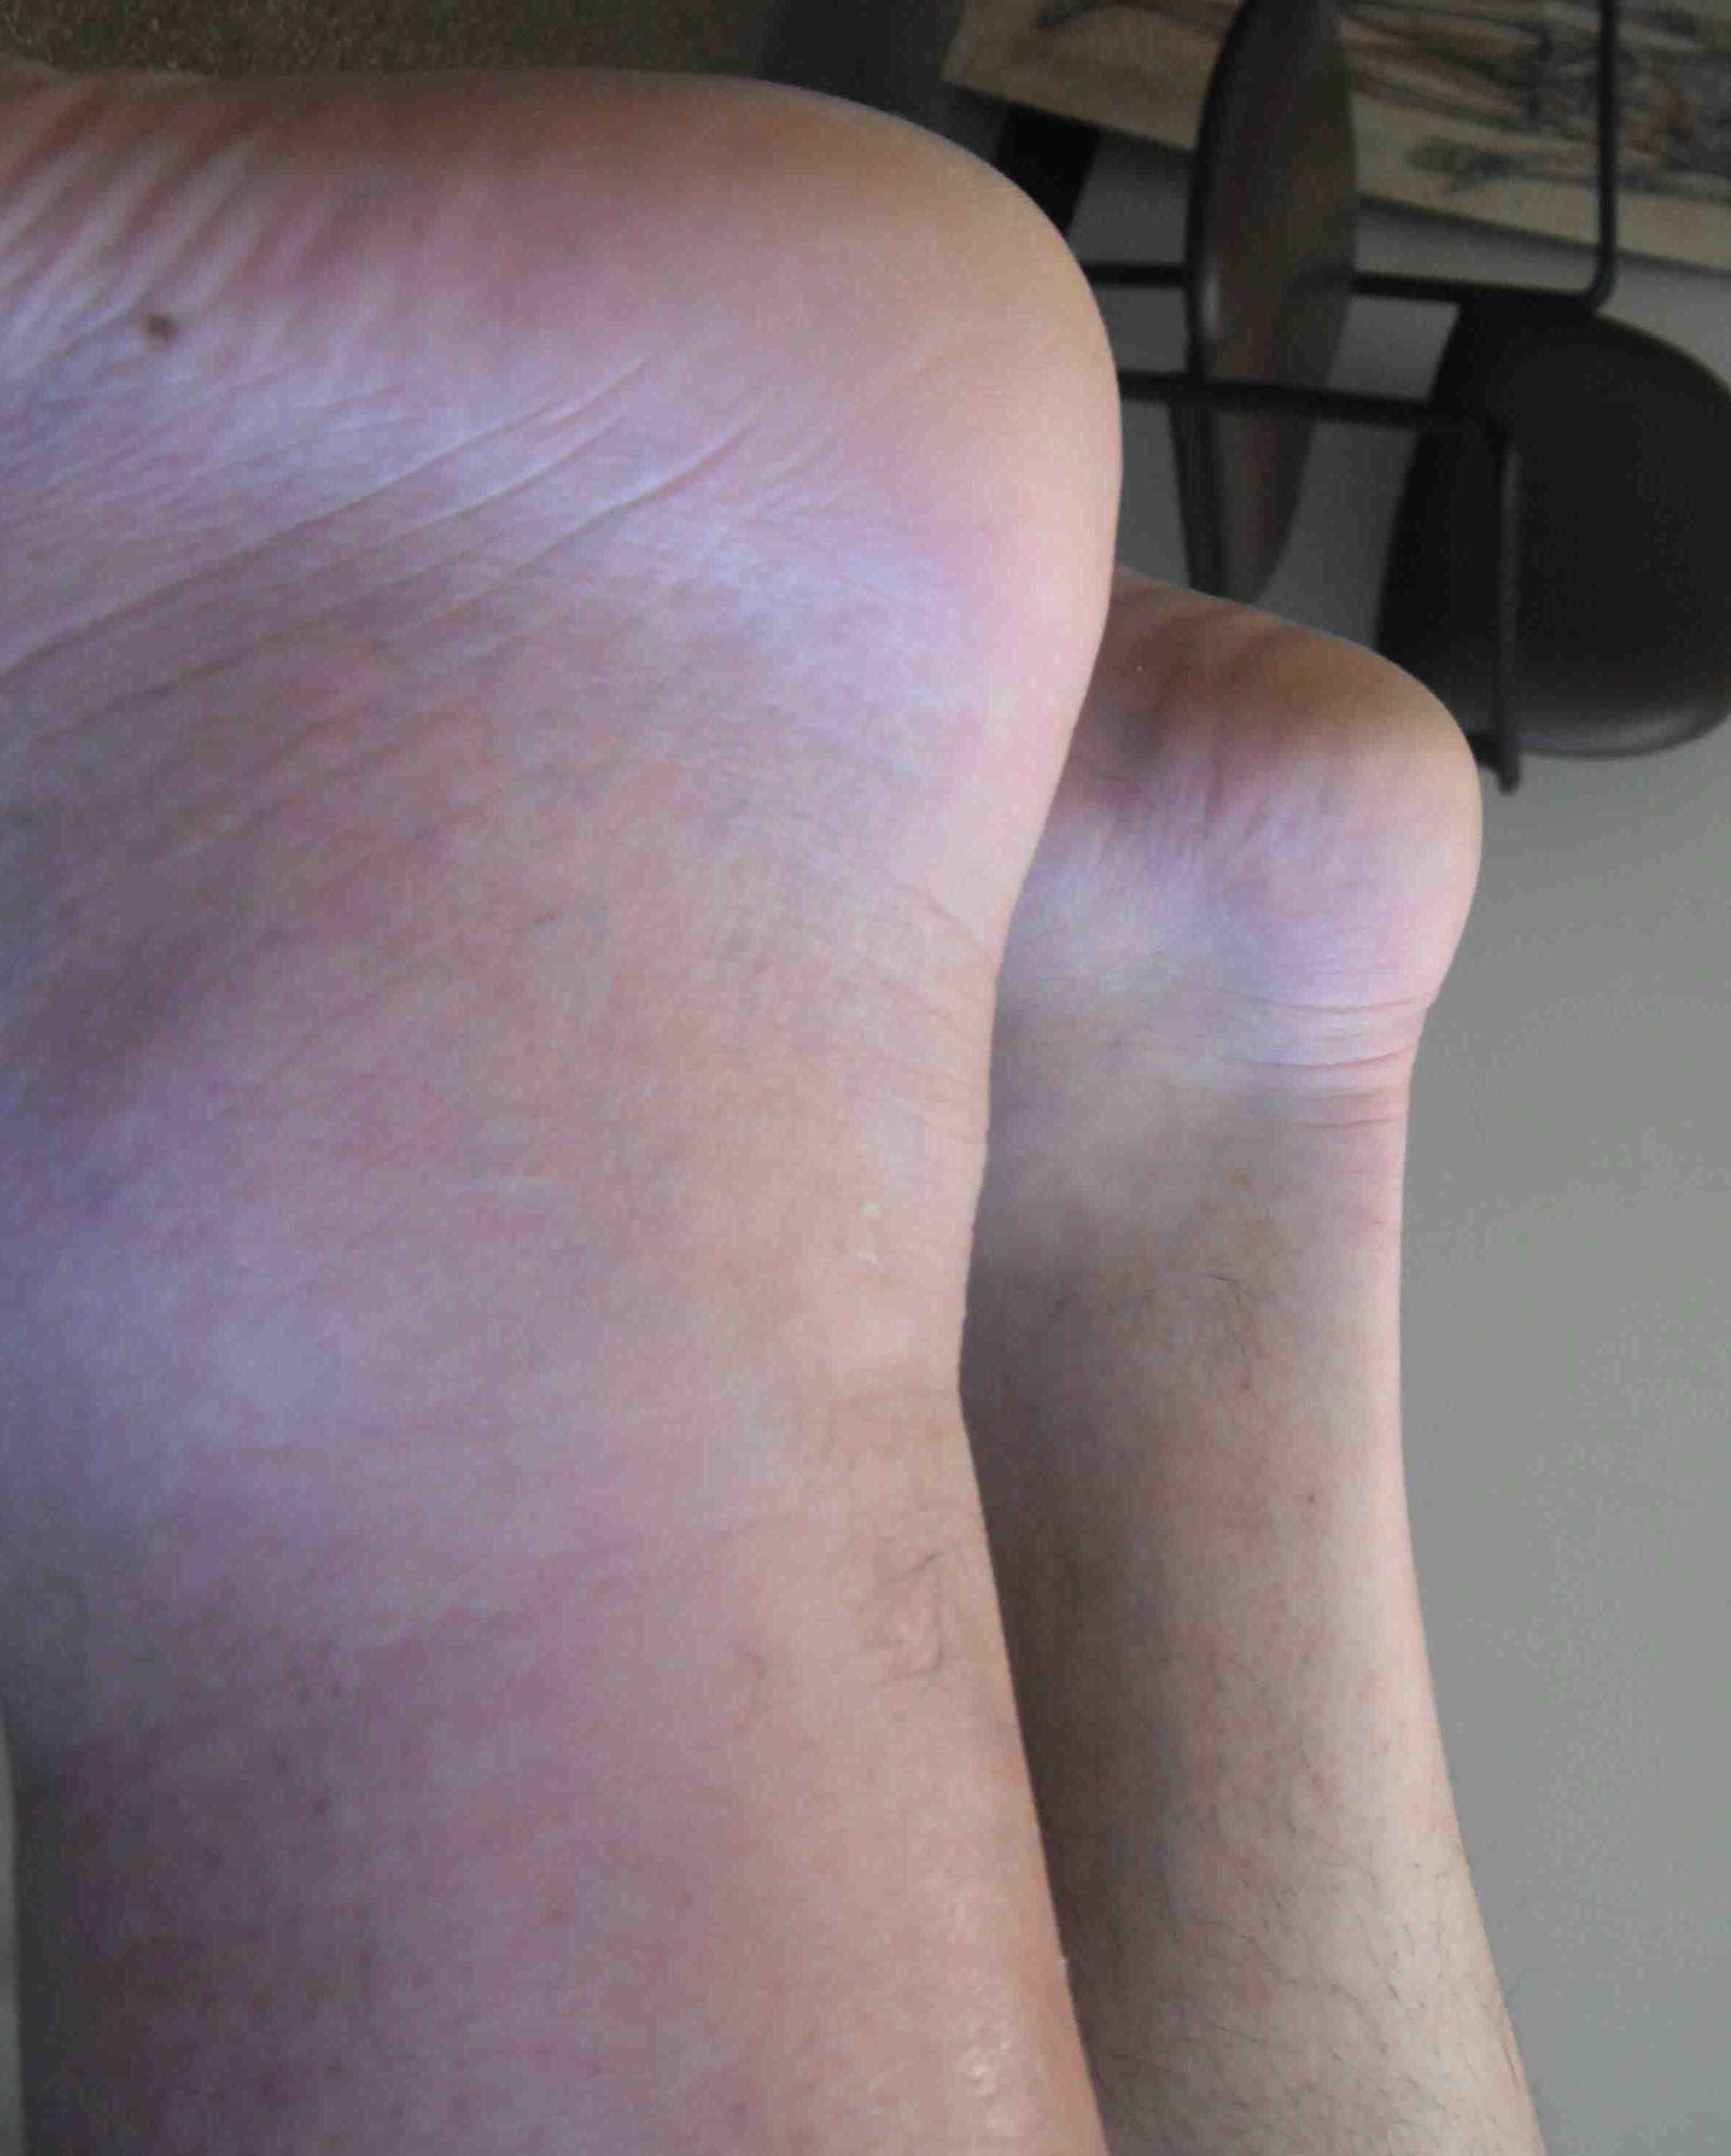

Chronic tear

Gap not palpable as gap fills with scar tissue

Excessive dorsiflexion compared with other side